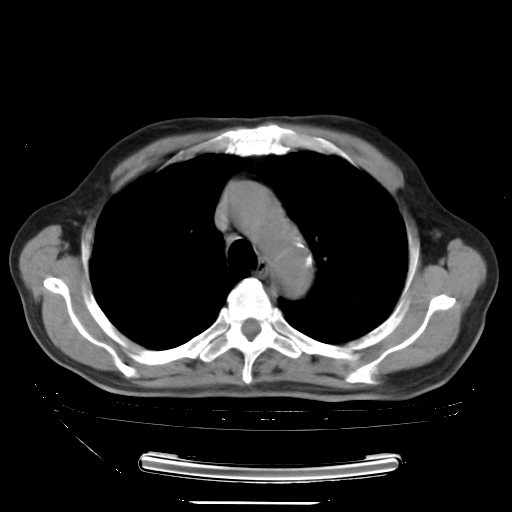

胸腹部CT,诊断意见:左上肺叶钙化灶、左侧胸膜局限性增厚并钙化、胆囊炎。描述部分肺组织呈磨玻璃样改变。

今天复查肺部CT,发现双肺广泛磨玻璃样改变。所以我把3月19日和5月9日相隔50天的肺部CT上传。请大家会诊。

2009年3月19日肺部CT片。

2009年3月19日肺部CT

大致读了系列胸部CT:纵隔窗无明显异常,肺窗:从4、27至今:主要是双肺中下野外带可见毛玻璃样改变,目前处于急性肺泡炎阶段,至于原因考虑1、结替组织或胶原血管性疾病所致?2、恶性疾病如恶组在肺部所致的表现或细支气管肺泡癌?3、药物或其它原因如肺蛋白沉着症所致肺泡炎目前不太可能?总之,明天就去请我院的呼吸科、感染科、血液科和临免专家会诊哈。